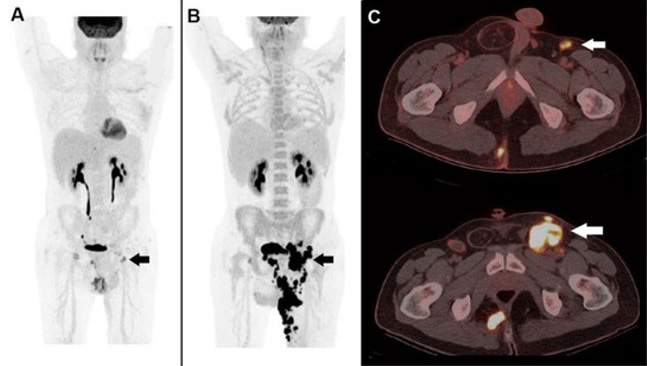

02. 18F‑PSMA

Targets PSMA to detect prostate cancer at staging and recurrence, delivering high‑contrast pelvic imaging.

04. 68Ga-PSMA

PSMA-targeted PET imaging agent for prostate cancer diagnosis, treatment response assessment, and recurrence detection.